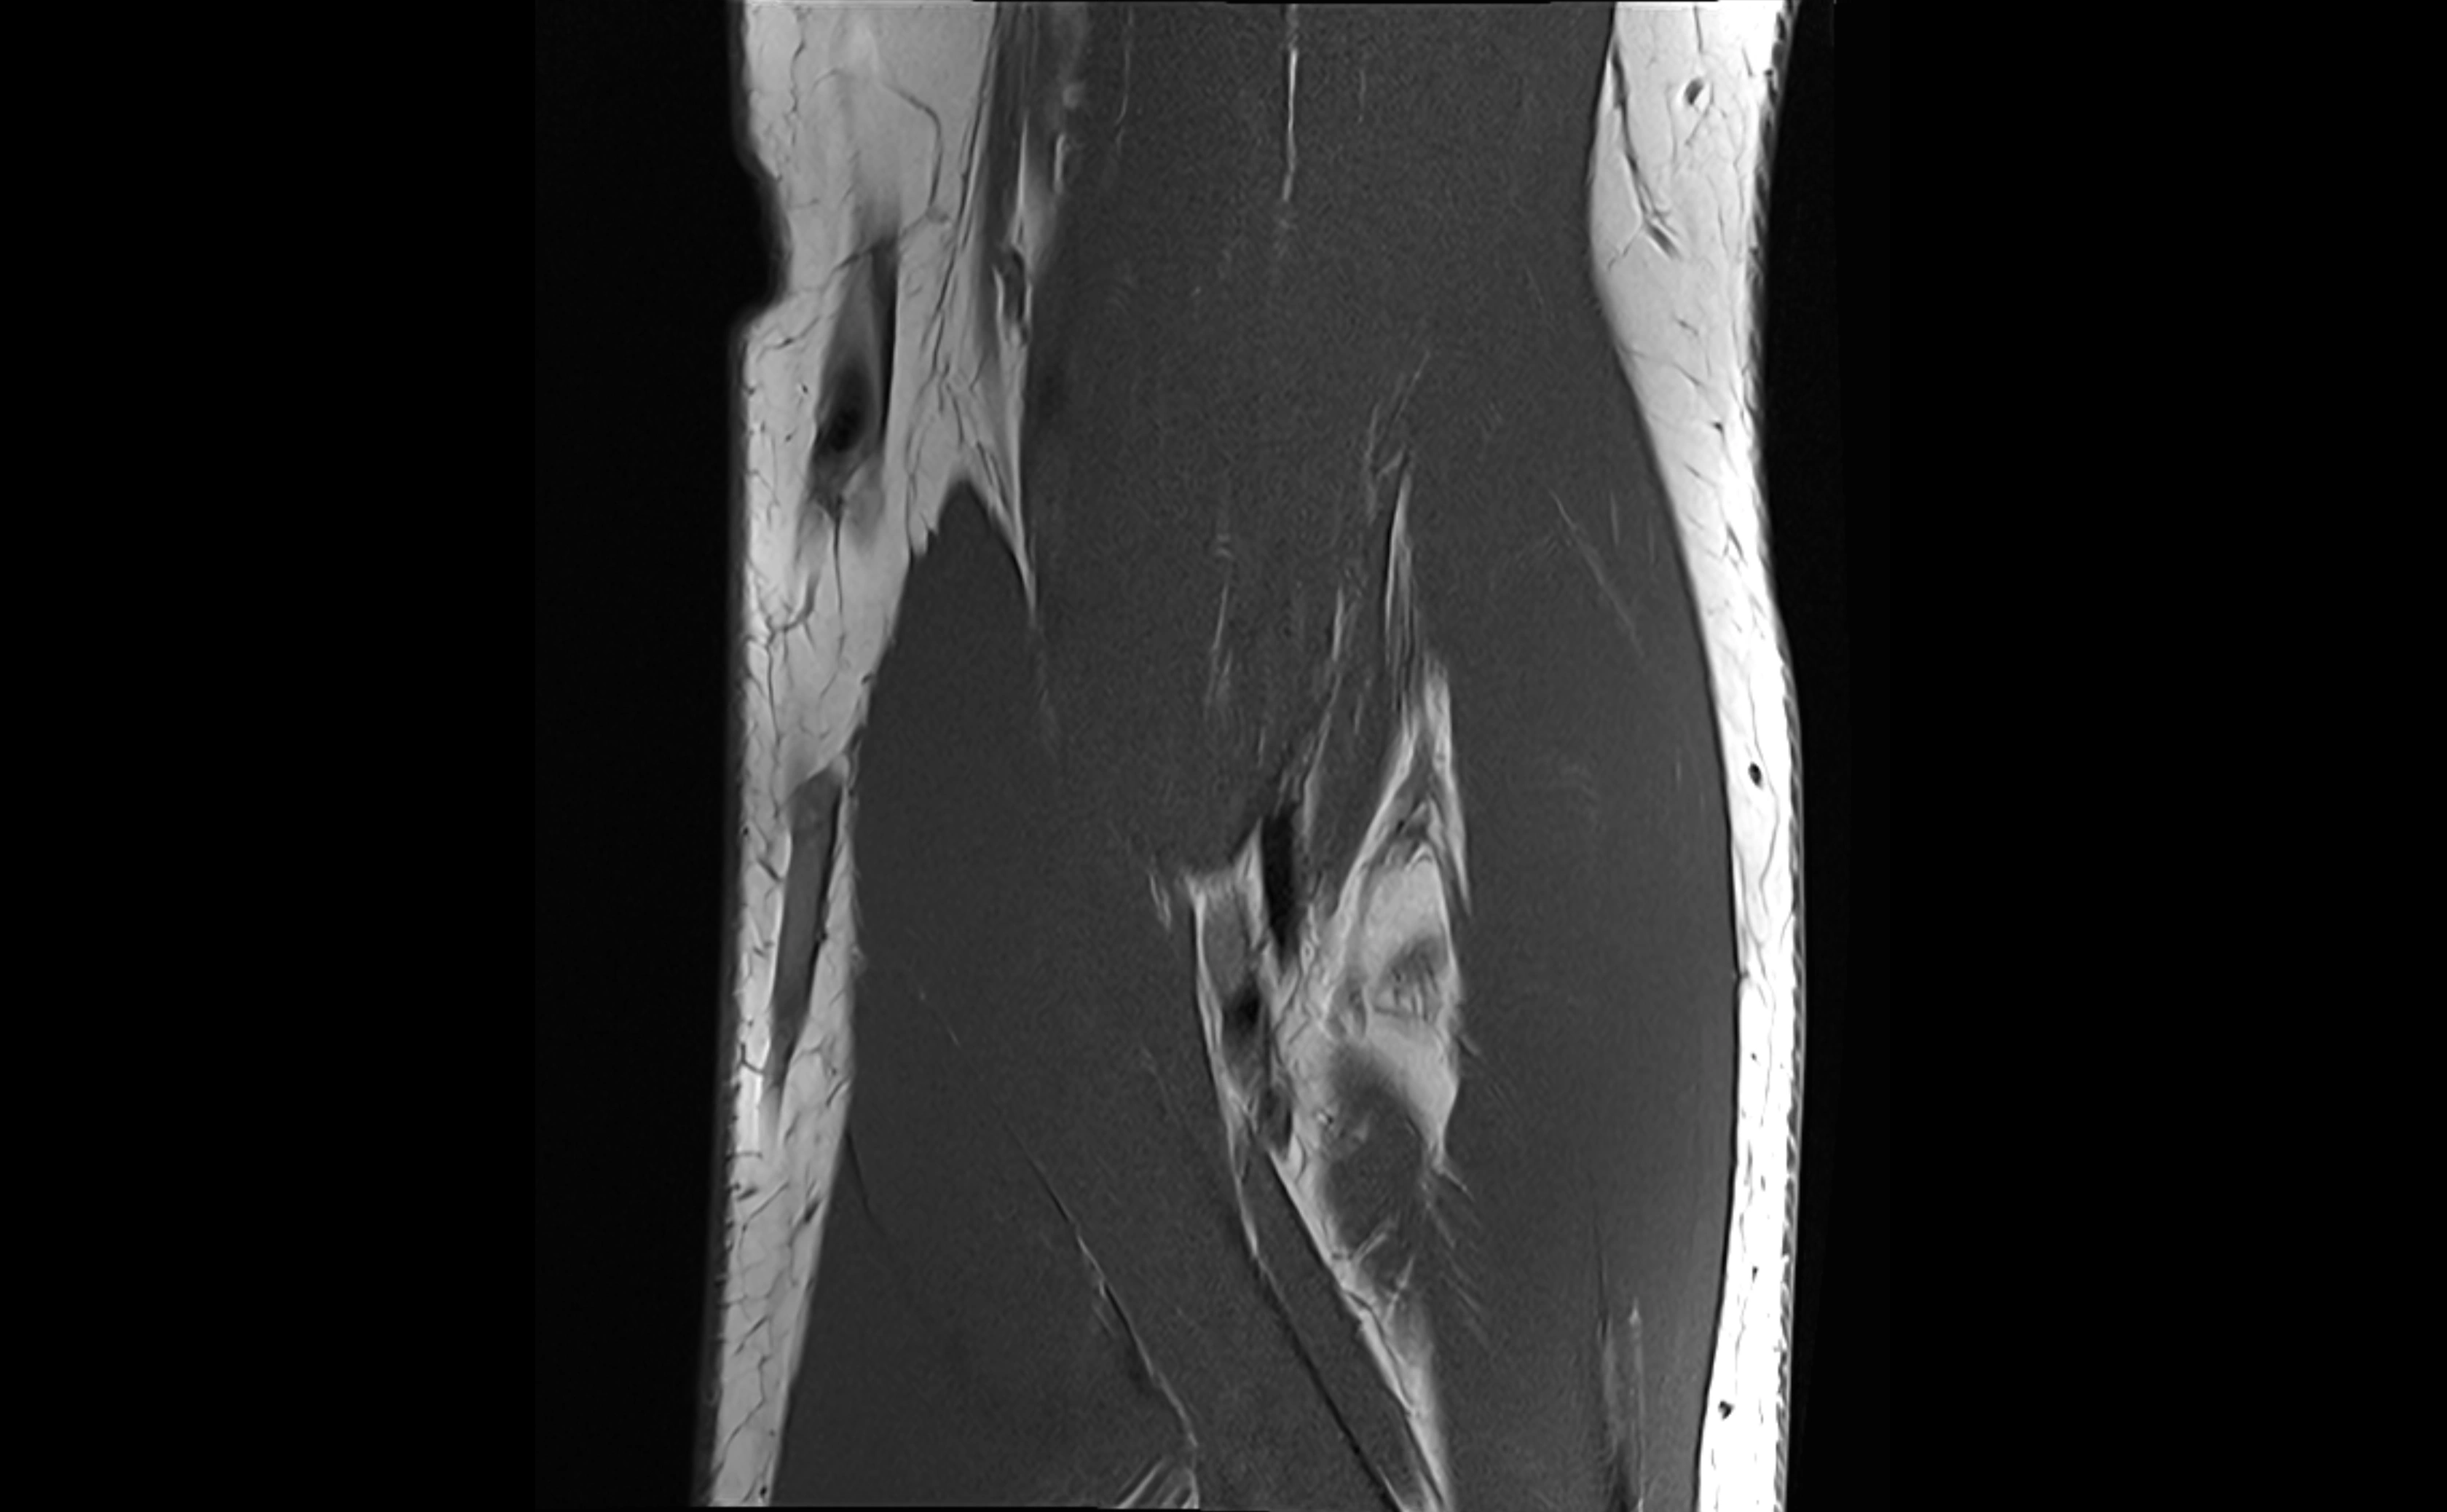

MRI images

image